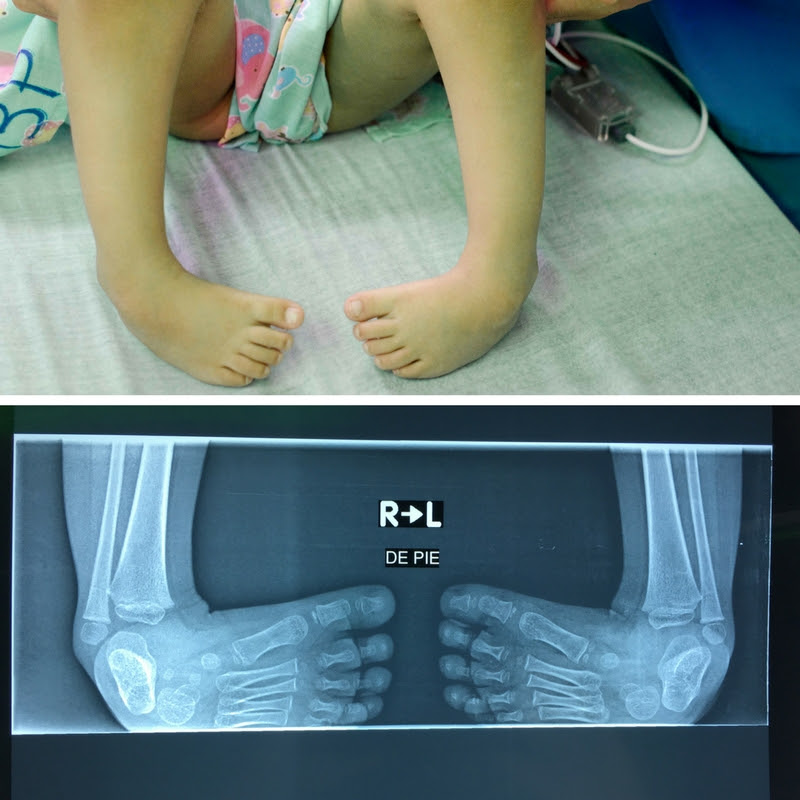

On Wednesday, a gorgeous little girl named Elena came in for a consultation with surgeons. Though she had missed the clinic day, her condition was so severe that CAMTA decided to add her to the surgical list for the week. During her assessment, she agreed to be photographed and was an absolute star for the camera. As soon as we took off her socks to photograph her feet, her demeanor changed drastically. She was reluctant and shy to show us her feet. She kept repeating her feet were “ugly” and “not real feet”. Her deformity was such that she had developed an alternate way of walking: knee-walking. Despite the odd position of walking on her knees, she was more agile on her knees than on her feet.

On the morning of her surgery, she reacted the same way towards pictures, telling us that she had “monsters instead of feet”. Those were quite harsh words considering Elena is not even 3 years old. Knowing she perceived herself so monstrously despite her young age just confirmed how much the surgery would change her life: both for her ambulation and her confidence.

Elena's feet, photographed for our files while she was under anesthesia.

t is quite rare for North American surgeons to see such a severe case of club feet. In Canada, children who are born withthis condition are usually treated in infancy, with a non-invasive procedure using Ponsetti casts. To document the procedure, instead of forcing her to have her feet photographed, her parents agreed that taking photos while she was under anesthesia would be less unsettling.

Closing up – Suregons inserted pins into Elena's feet to straighten them out. The pins will stay in for some time and will be protected by the cast. When they sutured the incision, we could already notice how the feet were positioned at a more natural angle.